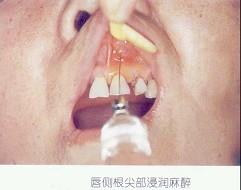

松动的乳牙拔除宜采用的麻醉方法是 ( )

- C.表面麻醉

- D.浸润麻醉

C